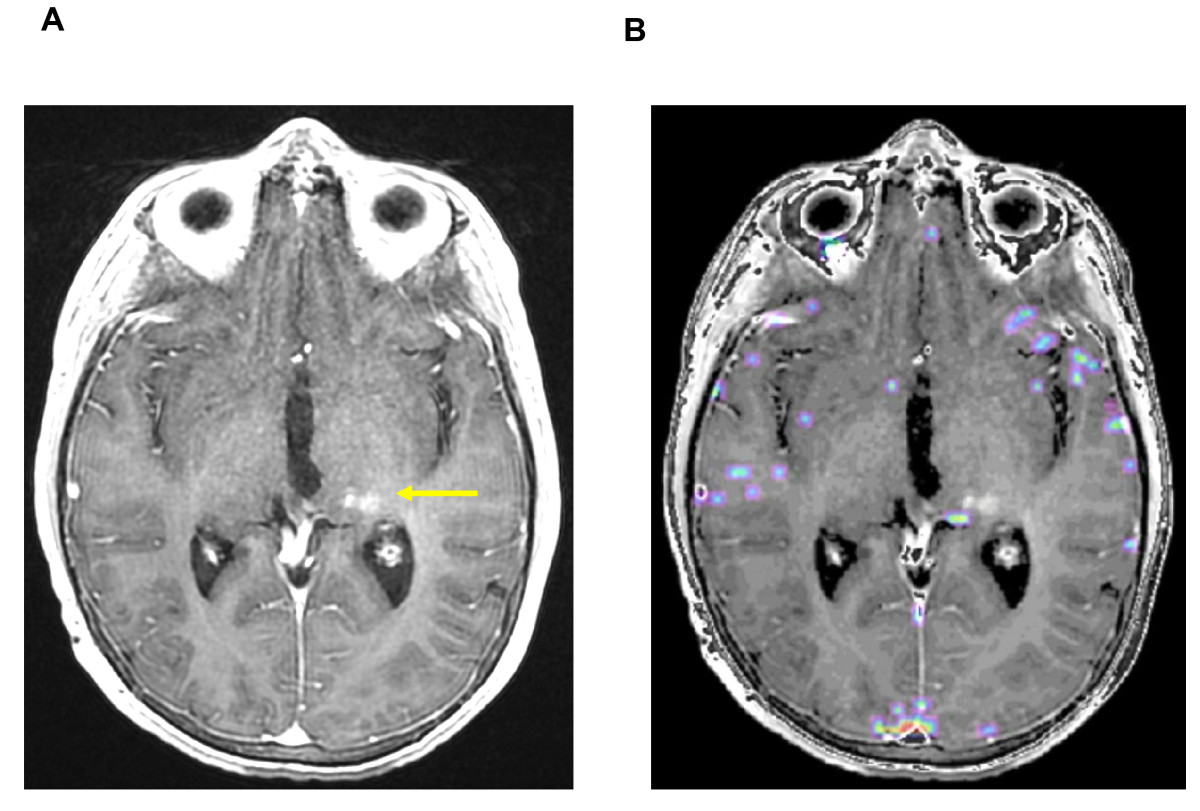

Figure 2. Conventional MR imaging before and six months after exclusive Proton therapy.

[A] T1-weighted transaxial MR image after administration of intravenous (iv) Gd-DTPA, one week before radiation. [B] The same sequence, six months after the end of irradiation (54 Gy), showing a strong contrast enhancement with a subtle mass effect (yellow arrow).

Figure 3. Six months after irradiation: superimposed MR images with T1-weighted sequence after iv Gadolinium injection and co-registered Perfusion (left) and Permability maps (right).

[A] Gradient-echo axial image with color overlay map showing no focus of hyperperfusion in regard of the strong contrast enhancement [B] The superimposed Permeability map with a strong microvascular leakage (yellow arrow) strictly corresponding with the enhanced area in the T1-weighted sequence.

Figure 4. Nine months after irradiation: complete disappearance of the contrast enhancement (left) and no detectable Permeability (right).

[A] T1-weighted transaxial MR image after administration of iv Gd-DTPA and [B] the superimposed Permeability map, with no contrast enhancement or detectable microvascular leakage. To be noted, a subtle hypersignal, pre-existing to the irradiation, as a post-operative modification (yellow arrow).

In order to more accurately differentiate tumour recurrence from radiation-induced changes, a DSC-MRI was performed as described previously(8)(9). The T2* sequence was used in order to assess simultaneously perfusion and permeability characteristics, as recently proposed for predicting risk of recurrence in adult low-grade gliomas(10). In this case, the typical combination of a focused area of high permeability strictly superimposed on the contrast enhancing lesion combined with the absence of high perfusion estimate in the same region (Figure 3) was compatible with post-radiation modifications, as recently suggested by Hu et al. They found a direct correlation between image-guided tissue histopathology and localized DSC perfusion MR imaging measurements in a series of adult high-grade gliomas(11). Consequently, we favoured the hypothesis of a delayed radiation injury and began a treatment with oral steroids (prednisone) at one mg/kg/d for one month before clinical and radiological reappraisal. After one month, decrease in size of contrast enhancement became significant while the patient remained asymptomatic. Steroids were therefore discontinued. Gradual improvement continued on conventional MRI and disappearance of both contrast enhancement and high permeability area strongly suggested a pseudo-progression rather than recurrent disease. Follow-up MRI at nine months post-RT showed a complete resolution of the gadolinium uptake and no detectable microvascular leakage (Figure 4). At last follow-up, patient is still in complete remission, more than two years post-RT.